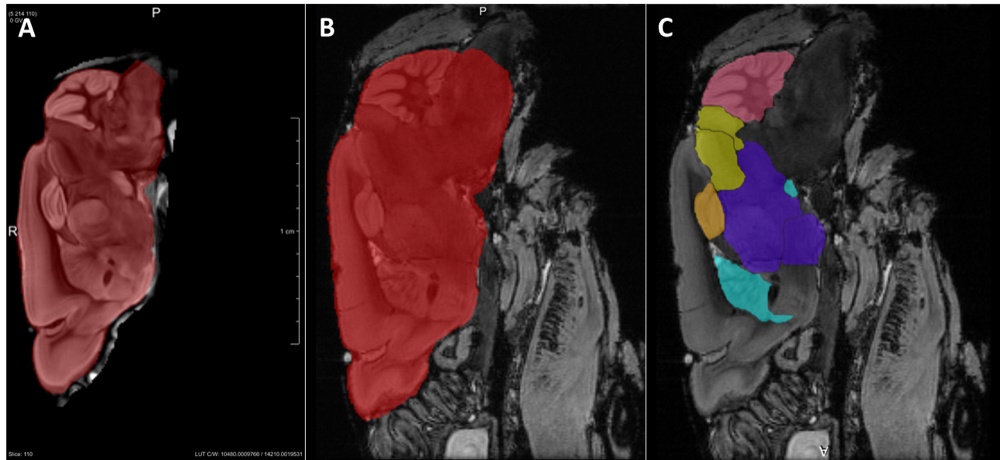

Chapter 5 Figure 1Ex vivo 3D imaging of the mouse brain with MRI and GT-DOTA contrast. The template brain in the sagittal imaging plane with whole brain label is shown in red (A). The labels were propagated to each of the registered individual datasets. Examples are shown for the whole brain (B), cerebellum (pink), colliculus (yellow), hippocampus (orange), combined thalamus and hypothalamus (purple) and basal ganglia (light blue) (C).